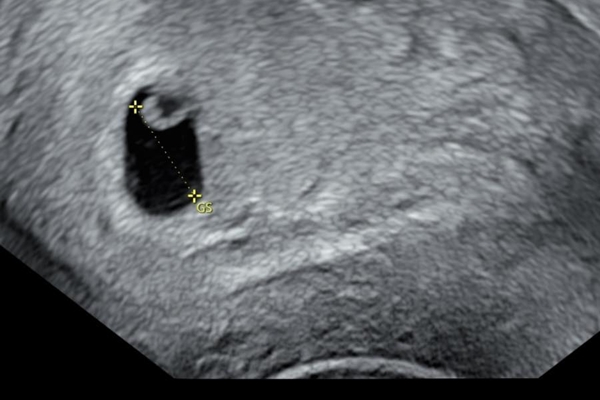

沒想到,1月6日傍晚開始少量出血,「過2小時後出血量變多開始腹痛,就立刻去急診,在醫院時陸續有排出血塊,照了陰道超音波確認胎囊大小與半個月前產檢時一樣,目前的處置就是回家休息吃止痛藥,等體力恢復後回台灣做後續。」